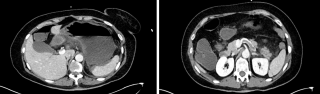

An 82-year-old otherwise healthy man was referred for evaluation of an incidentally detected left adrenal mass. The patient was asymptomatic with no clinical signs of catecholamine excess, hypercortisolism, hyperaldosteronism or B-symptoms. Initial CT scan revealed a 44 × 42 mm lesion, which increased to 50 × 46 mm within three months and suspicious washout characteristics (Figure 1). Endocrinological work-up showed a pathological dexamethasone inhibition test, while metanephrines and aldosterone testing was normal. Tumor markers (AFP, β-HCG) were unremarkable. A hormonally active adrenal adenoma with autonomous cortisol production was suspected.

After discussion at the interdisciplinary tumor board, robotic-assisted adrenalectomy was performed (Figure 2). Complete resection was achieved without complications, the patient was discharged on the third postoperative day.

Histopathological examination showed a Sertoli cell tumor with complete excision and no evidence of local infiltration or malignancy (Figure 3).